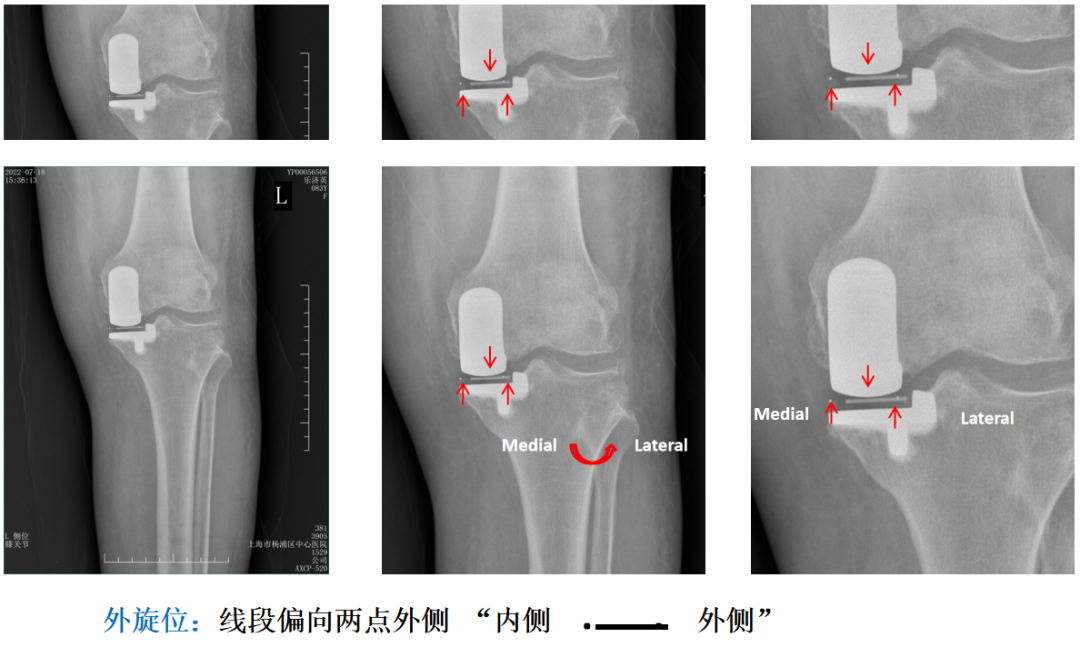

Bearing 内旋( X-ray正位)

Bearing 外旋( X-ray正位)